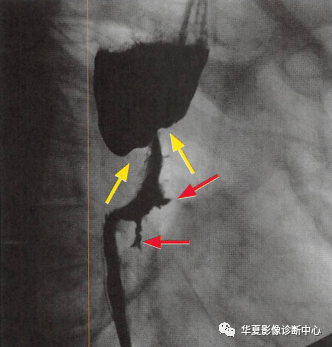

食管癌在钡餐造影下的一种表现之一,显示食管局部不规则狭窄(黄箭头:玫瑰花花干),近端食管扩张(萎陷的玫瑰花朵),两个不规则线状溃疡(红箭头:玫瑰花叶/刺),形似黑色玫瑰花,小编原创命名为:“黑色玫瑰花征”,帮助记忆,加深映像

进展期食管癌的典型表现为肿块所致狭窄,伴有“肩胛征”和不规整轮廓。较少见的串珠样表现可与静脉曲张混淆,但肿瘤并不会因蠕动波而改变形状,而静脉曲张则都有改变。